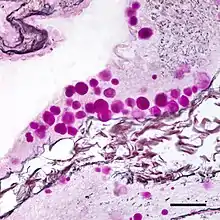

Corpora amylacea

Corpora amylacea (CA) (from the Latin meaning "starch-like bodies;" also known as wasteosomes[1]) is a general term for small hyaline masses found in the prostate gland,[2] nervous system,[3] lung,[2] and sometimes in other organs of the body.[4] Corpora amylacea increase in number and size with advancing age,[4][5] although this increase varies from person to person.[4] In the nervous system, they are particularly abundant in certain neurodegenerative diseases.[3] While their significance is largely unknown, some researchers have suggested that corpora amylacea play a role in the clearance of debris.[2][4]

The composition and appearance of corpora amylacea can differ in different organs.[4] In the prostate gland, where they are also known as prostatic concretions, corpora amylacea are rich in aggregated protein that has many of the features of amyloid, whereas those in the central nervous system are generally smaller and do not contain amyloid.[4] Corpora amylacea in the central nervous system occur in the foot processes of astrocytes, and they are usually present beneath the pia mater, in the tissues surrounding the ventricles, and around blood vessels.[3] They have been proposed to be part of a family of polyglucosan diseases, in which polymers of glucose collect to form abnormal structures known as polyglucosan bodies.[4] Polyglucosan bodies bearing at least partial resemblance to human corpora amylacea have been observed in various nonhuman species.[4]